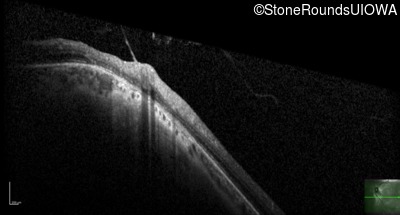

Age at visit: 41 years (Visit 2)

OD OS

This 41 year old woman was highly myopic as a child and experienced a rhegmatogenous retinal detachment OS at age 20.

Refraction OD:     -17.25 +1.00 x 93

Refraction OS:     -18.25 +3.50 x 56

The clinical features favoring the diagnosis of Sticker syndrome in this patient include extensive radial lattice degeneration, a personal and family history of rhegmatogenous retinal detachment, a history of cataract surgery before age 30 (and very high myopia before that), arthritis in her knees and hips and a slightly flattened mid-face.